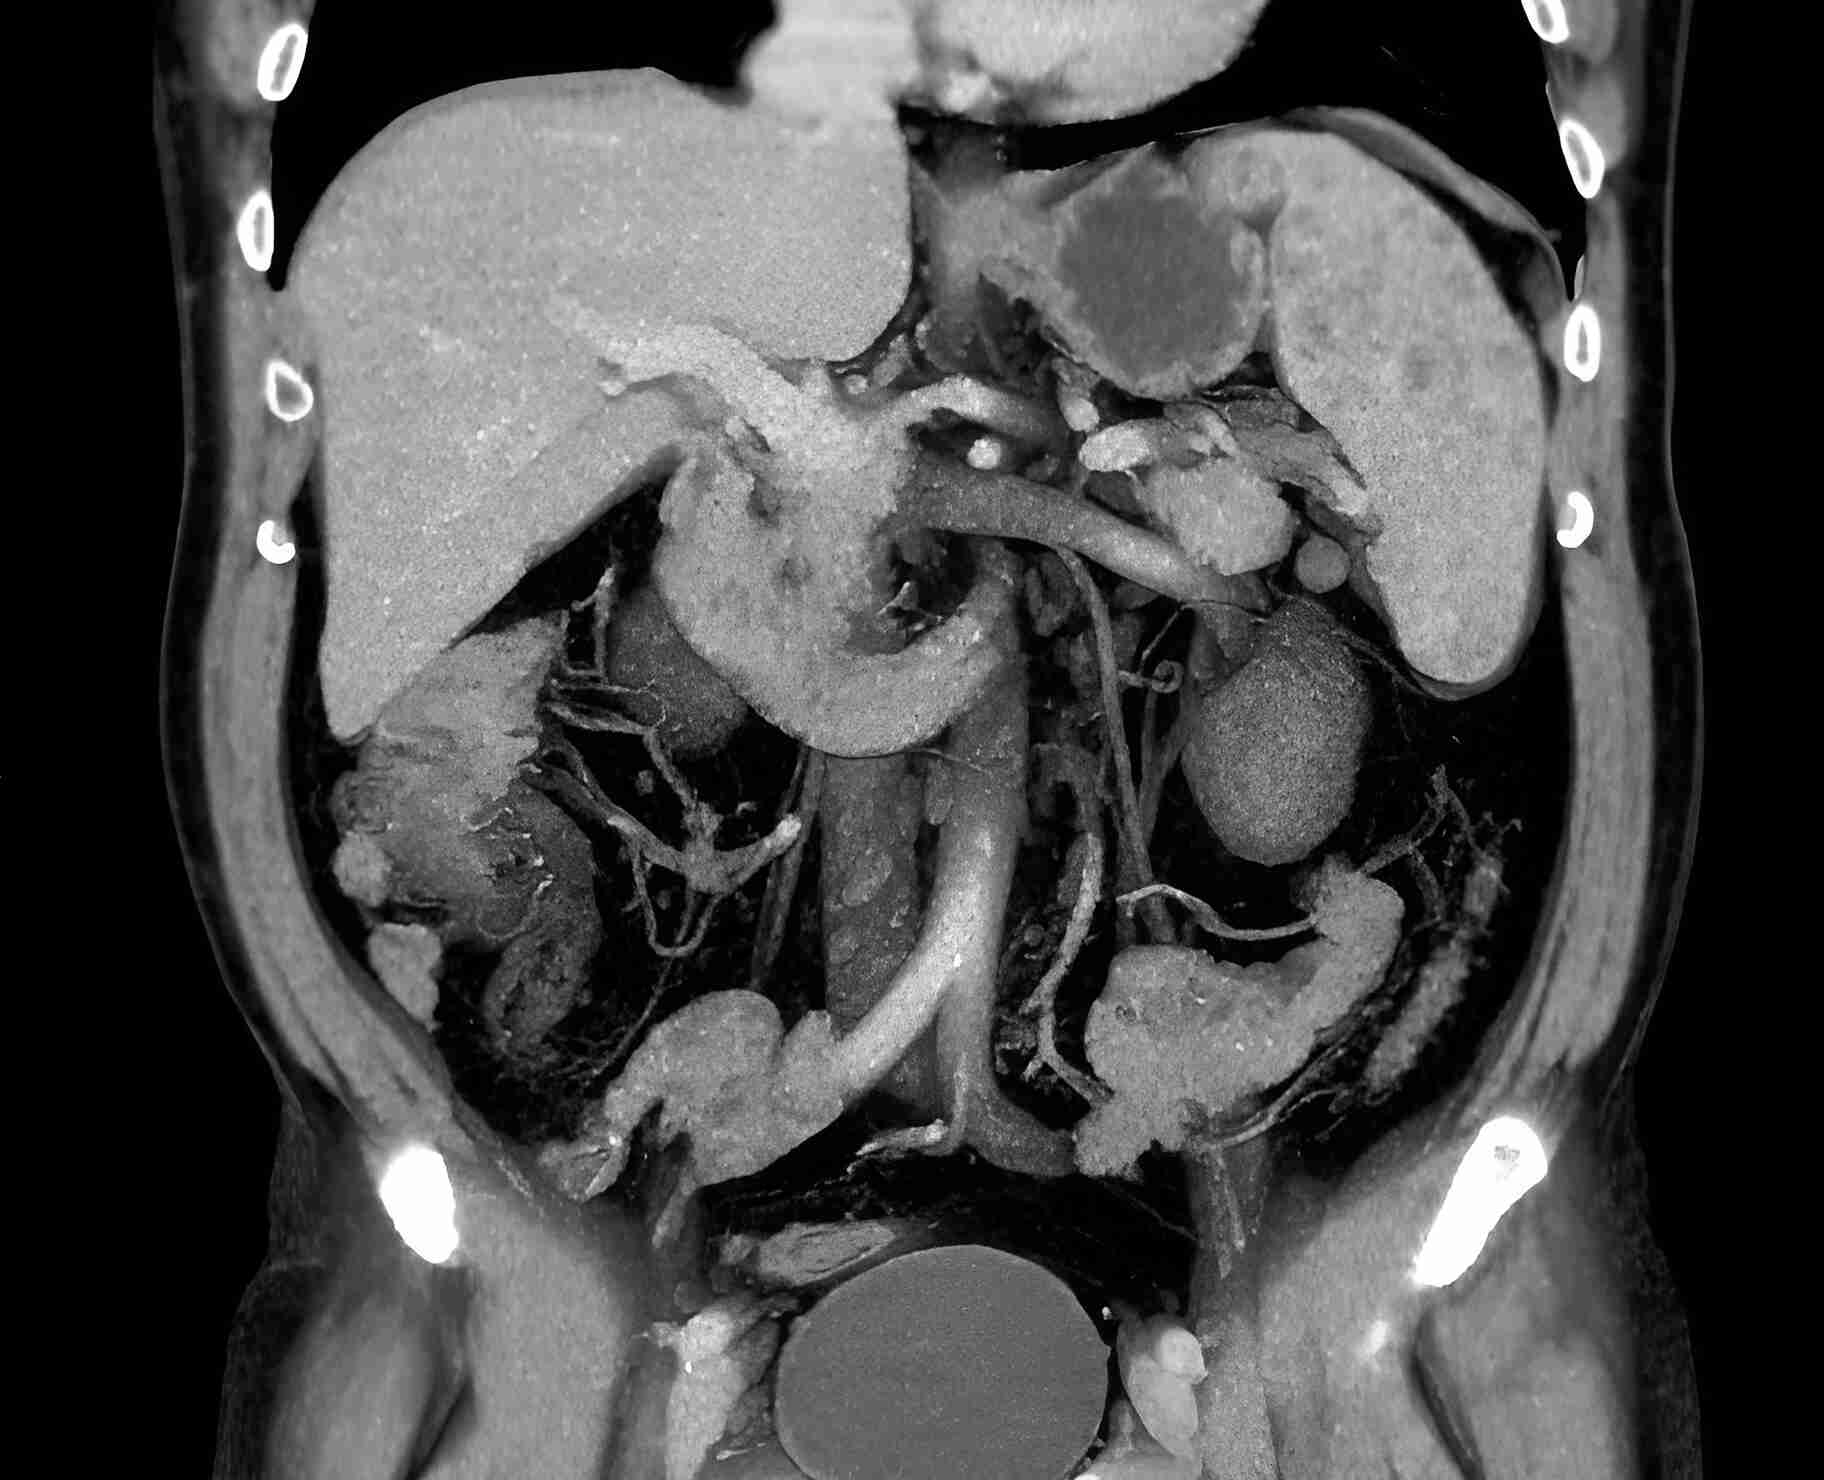

КТ ретроперитонеального фиброза: Изображения и диагностика